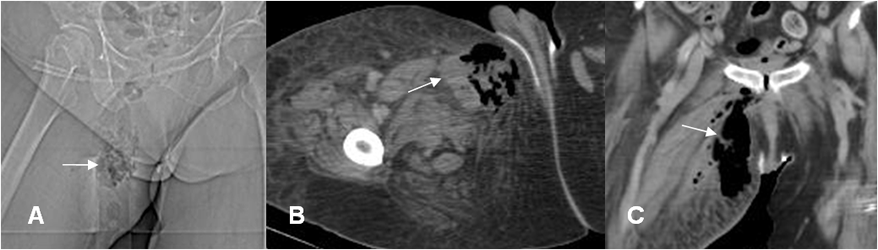

Fig 26 B. Miositis necrotizante.

A: Rx digital, B: TAC axial y C: TAC reconstrucción coronal. Igual paciente anterior, con mala evolución clínica. Se encuentra colección y abundante cantidad de aire en los tejidos blandos de la parte medial del muslo, por proceso infeccioso.

Hay prominencia de los tejidos blandos adyacentes.